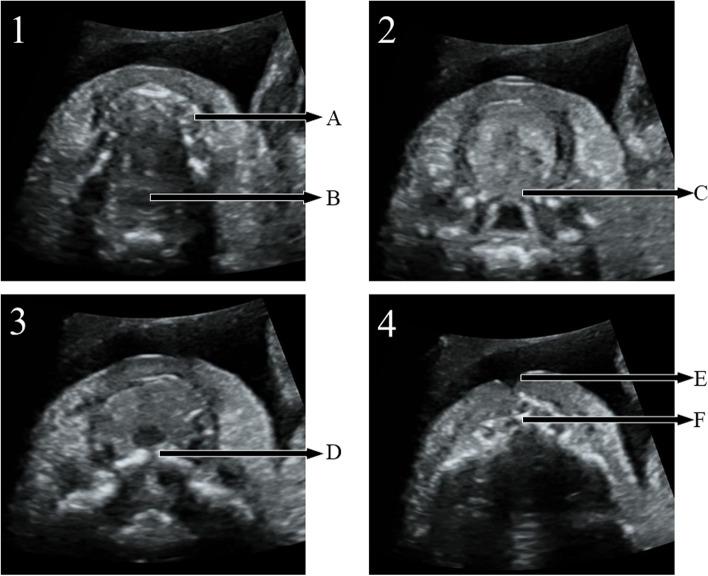

Prenatal diagnosis of cleft palate is still challenging. To describe a practical and efficient method, sequential sector-scan through oral fissure (SSTOF), to evaluate palate.

According to the characteristics of the fetal oral anatomy and ultrasonic directivity, we designed a practical method, sequential sector-scan through oral fissure, to evaluate the fetal palate, and the approach was verified efficiently by following up results of those fetuses with orofacial cleft who were induced because of their accompanied lethal malformations. Then, the 7098 fetuses were evaluated using sequential sector-scan through oral fissure. Fetuses were followed up after birth or induction to validate and analyze prenatal diagnosis.

RESULT

According to the scanning design, sequential sector-scan through oral fissure was performed successfully from the soft palate to the upper alveolar ridge in induced labor fetuses, and the structures were displayed clearly. Among 7098 fetuses, satisfactory images were obtained for 6885 fetuses and the remaining 213 fetuses' images were unsatisfactory because of fetuses' positions and pregnant women with high BMI. Among 6885 fetuses, 31cases were diagnosed CLP or CP, which were confirmed after delivery or termination. There were no missing cases.